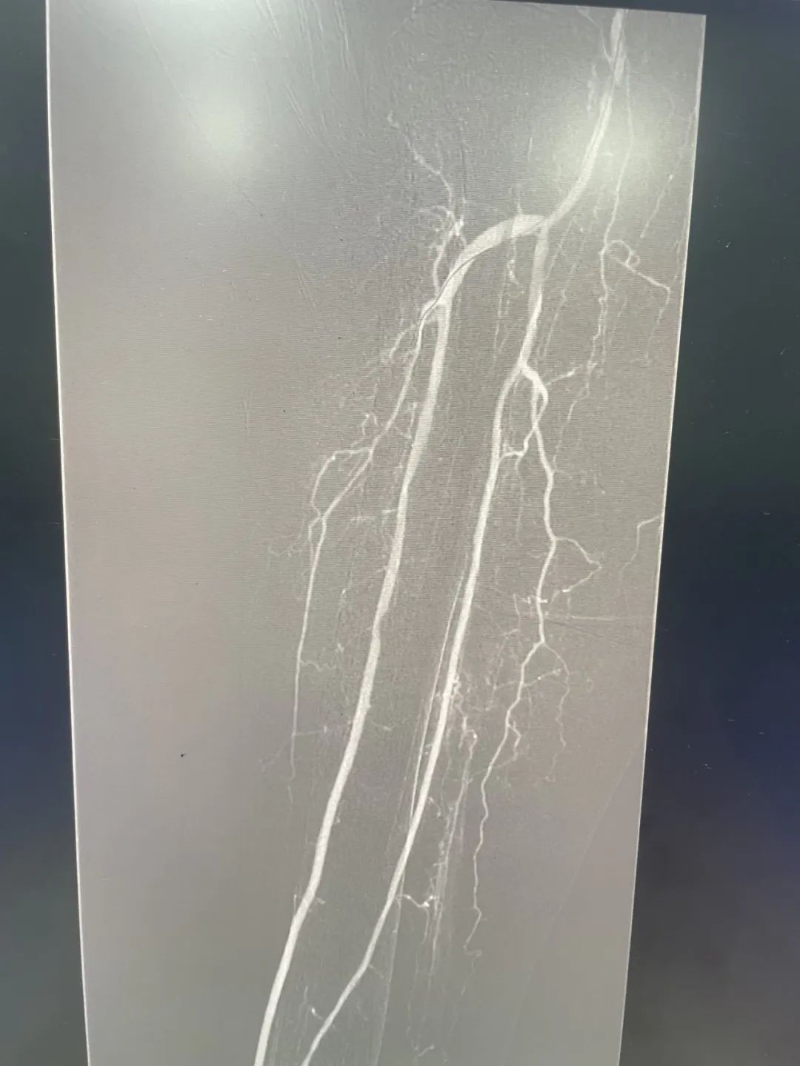

手術當日,在楊福周的全程指導下,惠州市中心人民醫院博羅分院(博羅縣人民醫院)手足/燒傷/整形外科主任郭洪海帶領吳細浩、陳亞軍等醫生精準定位患者下肢動脈狹窄部位,通過穿刺導管將球囊送至病變區域進行擴張,成功開通閉塞血管。術后影像顯示血流恢復通暢,患者肢體疼痛即刻緩解?!按舜问中g不僅解決了患者因疾病帶來的困擾,減輕了患者的經濟壓力,更為縣域內動脈閉塞性疾病治療提供了新方案?!睏罡V茉谛g后總結中高度評價了團隊的技術執行力,贊揚了手足/燒傷/整形外科的醫護人員專業素養和敬業精神。

【治療前后對比】

△治療前

△治療后